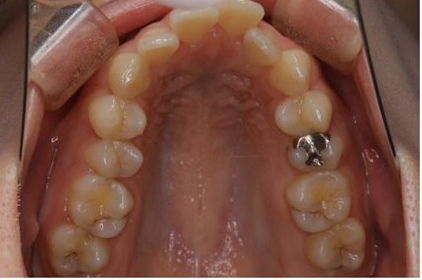

矯正歯科

症例集